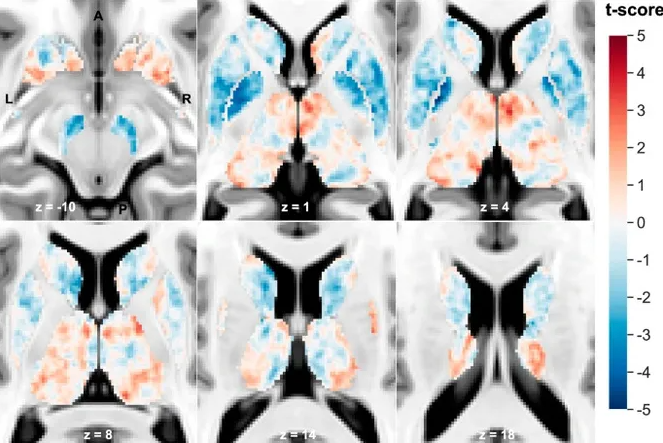

Карта t-оценки подкорковой магнитной восприимчивости (χ) на Т1-взвешенном шаблоне Монреальской неврологической визуализации (MNI) на уровне и ориентации аннотированного среза.

Исследователи провели магнитно-резонансную томографию мозга 85 пациентам с шизофренией и 86 здоровым людям. Более того, они использовали железочувствительное и диффузное МРТ.В результате ученые увидели, что по сравнению со здоровыми людьми, у пациентов с шизофренией в ключевых областях было:

Эти аномалии были особенно выражены в глубоких структурах мозга, таких как хвостатое ядро, скорлупа и бледный шар, которые вместе играют важную роль в контроле движений, эмоций и сложных форм поведения.